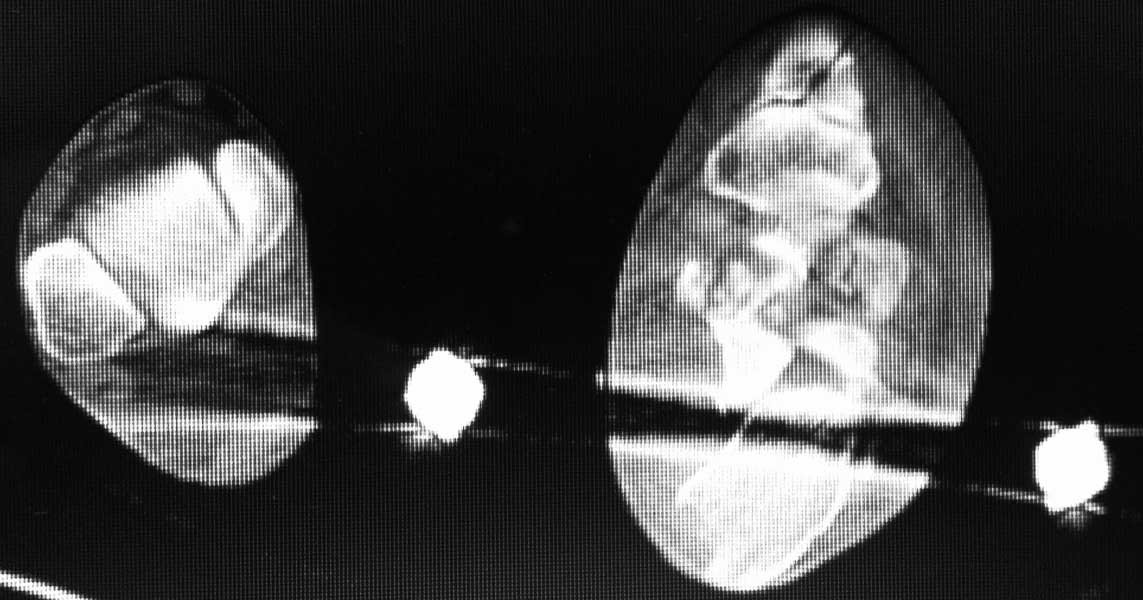

немного КТ

• Сообщения о Ортопедия и травматология